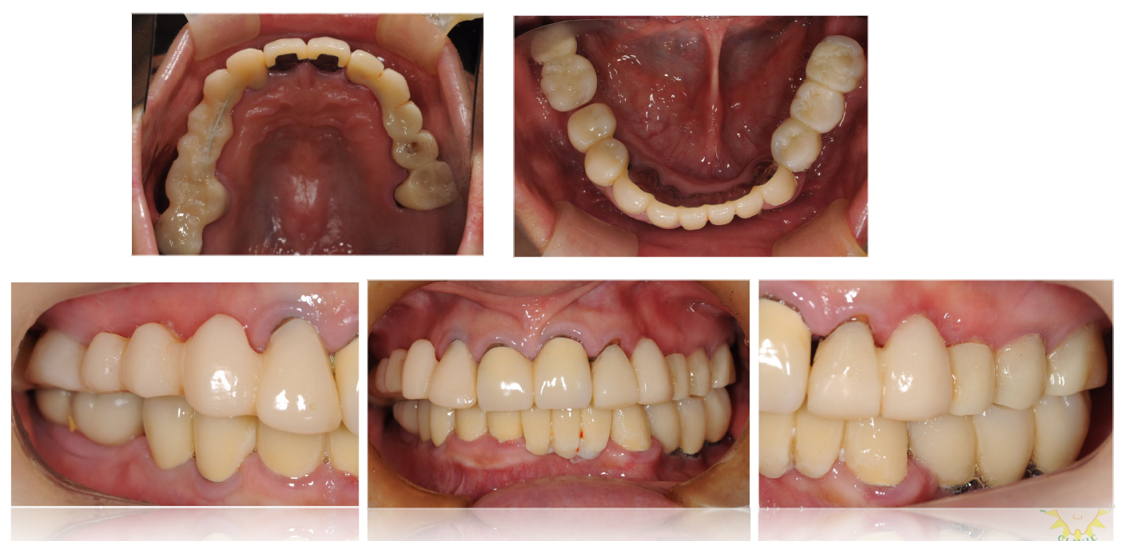

インプラント治療の症例6

(上下の歯が複数本ない・咬合崩壊)

治療前

治療後

| 診断名・主訴 | ①治療の続きをしてほしい ②インプラント希望 |

| 年齢 | 50歳 |

| 治療期間 | 3年間 |

| 治療内容 | インプラント治療 |

| 治療に用いた主な材料、設備機器 | 京セラFINESIAインプラント 上部構造:ジルコニアセラミック |

| 抜歯部位 | 右上8・6・2 左上5・6 |

| 治療費 | 約350万 |

| リスク・副作用 | 術後出血や腫れ |